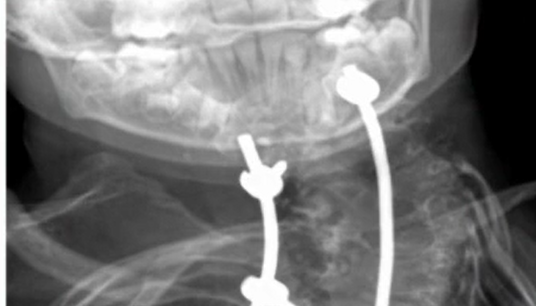

This video show the surgery of a 8-year-old boy with a severe congenital cervicothoracic spine malformation (Klippel-Feil syndrome) in combination with asymmetri...

Projekt 09-004

This video demonstrates a cervicothoracic instrumentation and fusion by a posterior approach after previous release by anterior approach. This led to a p...